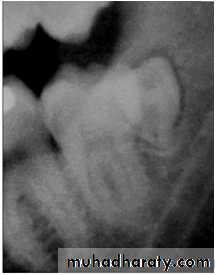

most often affects the mandibular 3rd molars &maxillary canines.

CAUSES: due to obstruction from crowding.

occasionally, may be due to an abnormal eruption

path, presumably because of unusual orientation of

tooth germ.